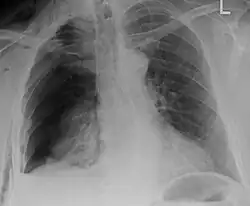

| An X ray showing multiple old fractured ribs of the person's left side as marked by the oval | |

Plain X-rays often pick up displaced fractures but often miss undisplaced fractures.[13] CT scanning is generally able to pick up both types of fractures.[13]

Illustration showing rib fracture at 3rd, 4th and 5th rib -

Right sided pneumothorax and rib fractures -